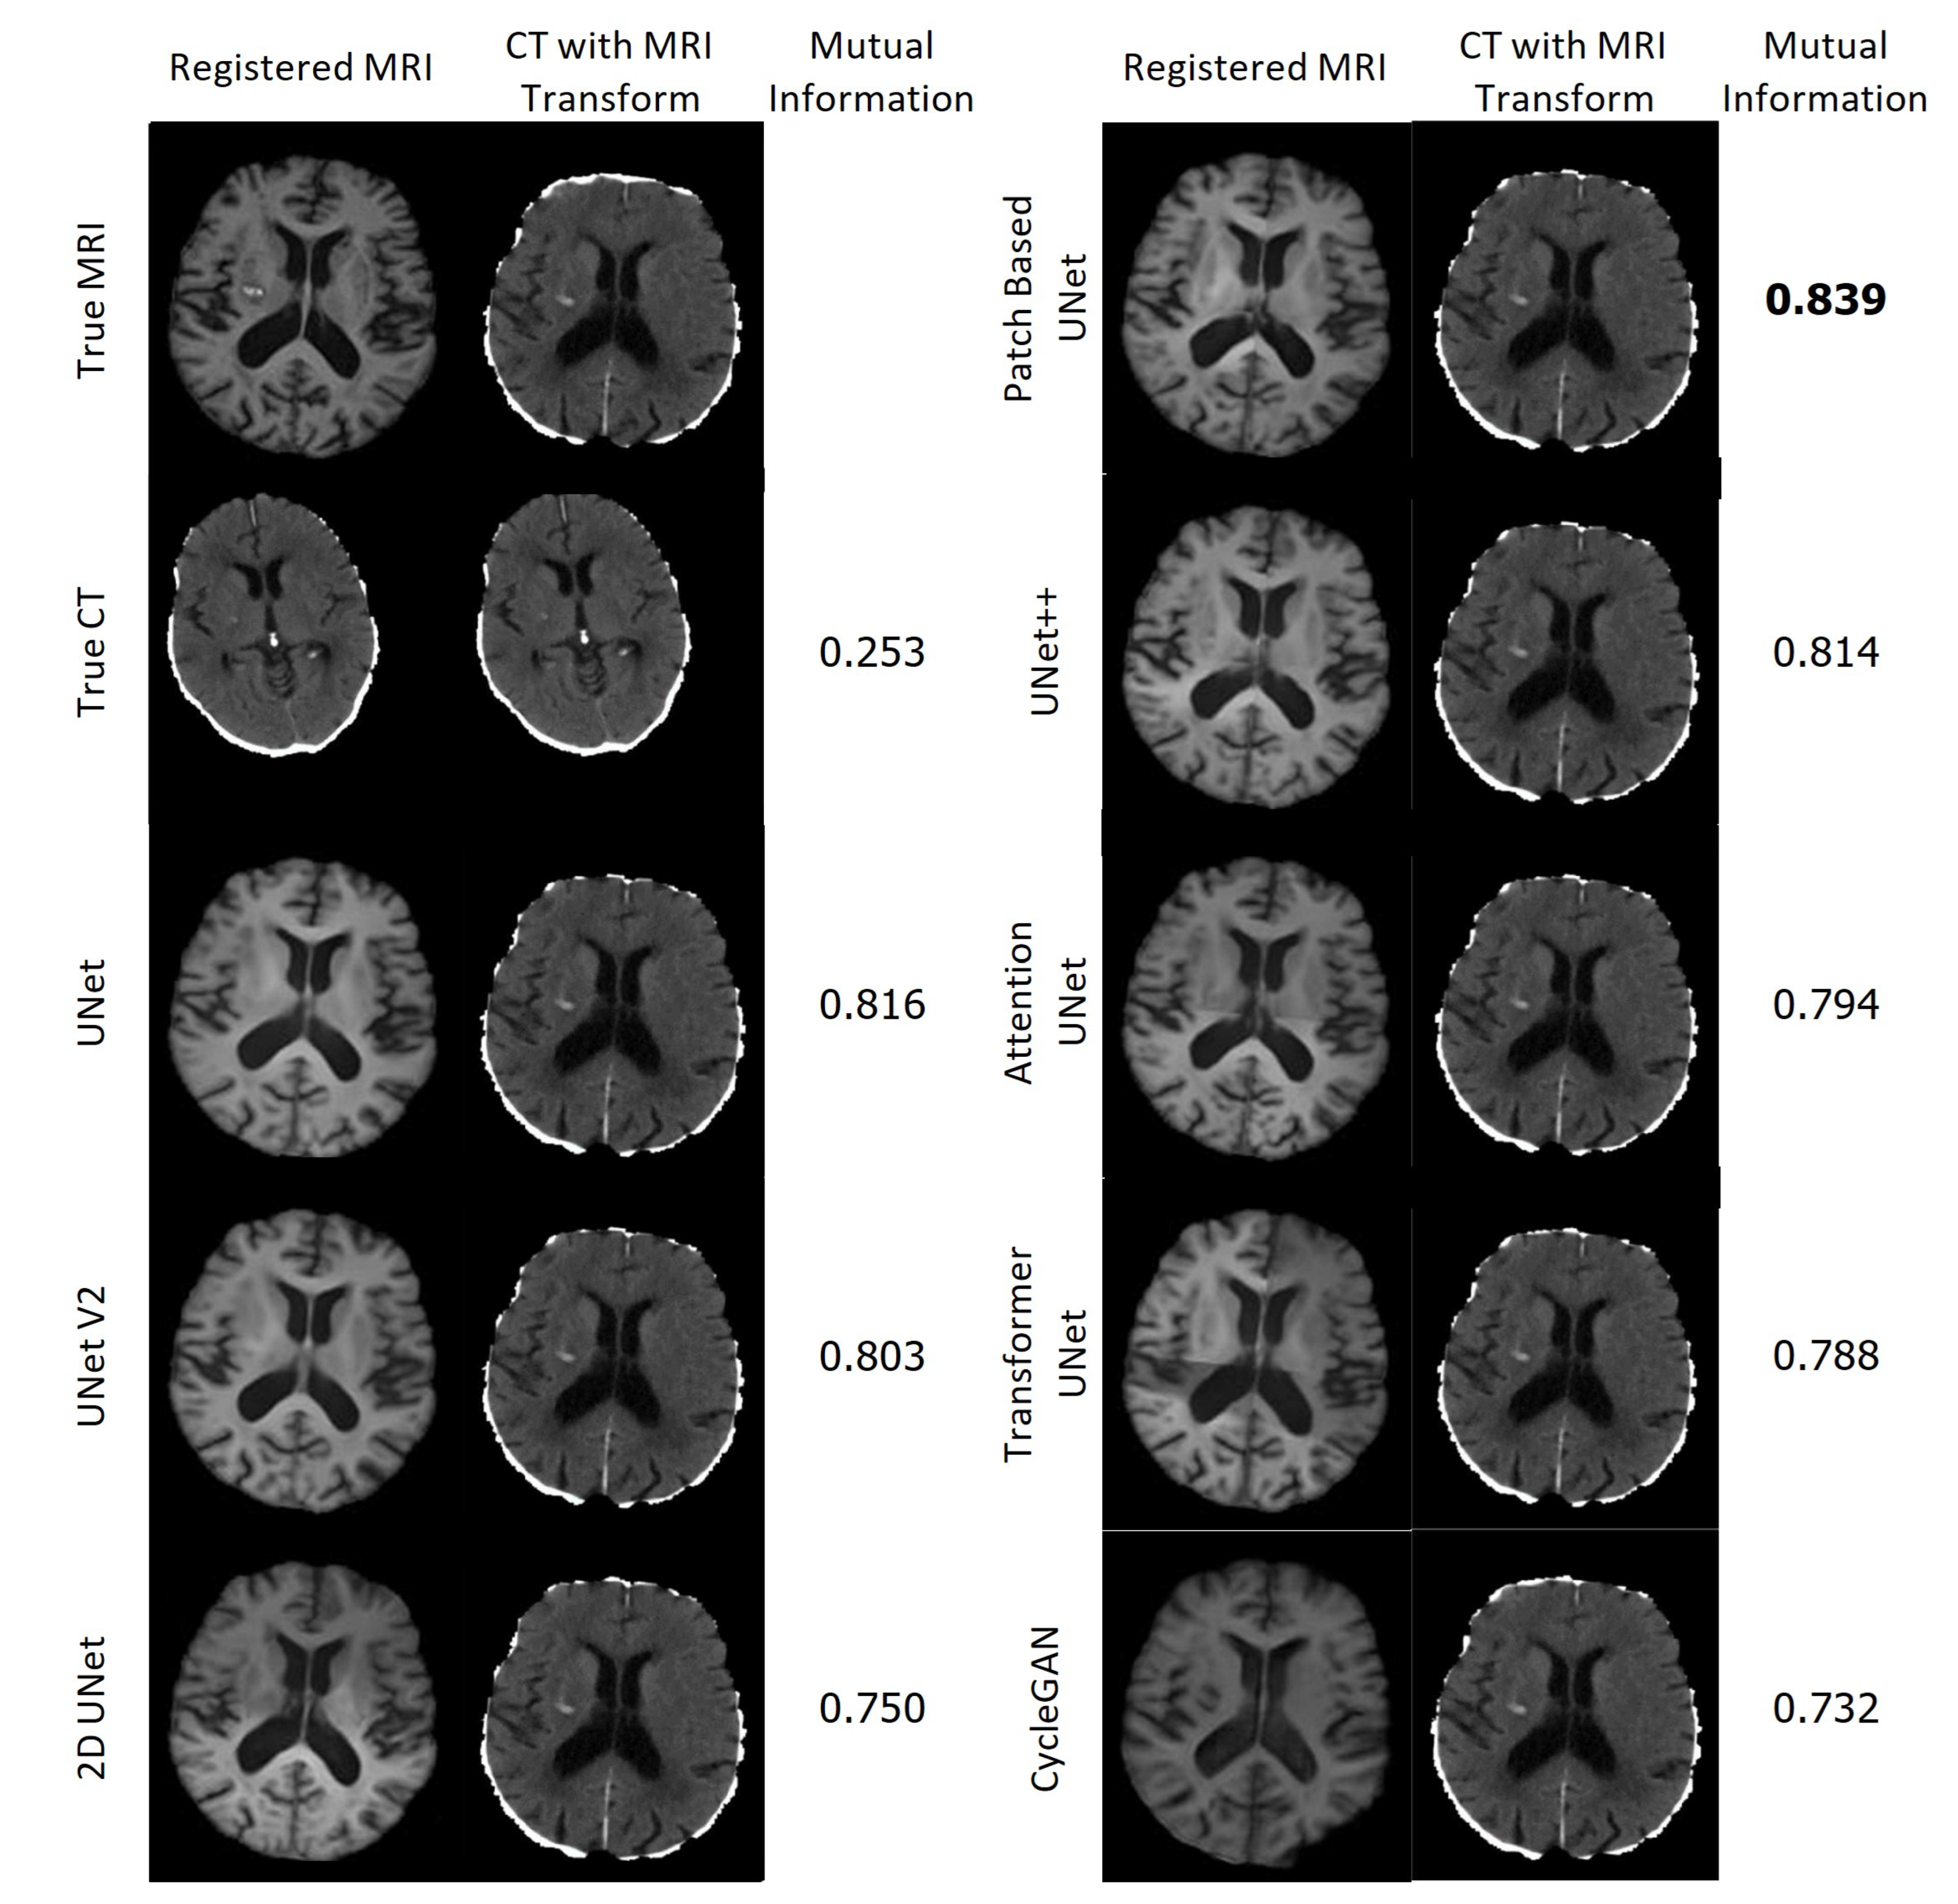

Figure 23 displays the resulting registrations for each MRI and the corresponding CT in the first column, along with the CT that underwent the associated transformation in the second column. The Mutual Information between the presented CT and the CT which underwent the True MRI transformation is provided for each case. Remarkably, all of the synthetic MRIs achieve a high degree of accuracy in aligning with the target MRI. In contrast, the CT scans were not aligned accurately and required significantly more time for calculating the transformation.

Figure 23. Registration of the True MRI and Synthetic MRIs of Patient H and the associated registrations of the CT of Patient H.